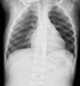

Rachitic rosary

The prominent knobs of bone at the costochondral joints of rickets patients are known as a rachitic rosary or beading of the ribs. The knobs create the appearance of large beads under the skin of the rib cage, hence the name by analogy with the beads of a Catholic Christian rosary. [Source: Wikipedia ]